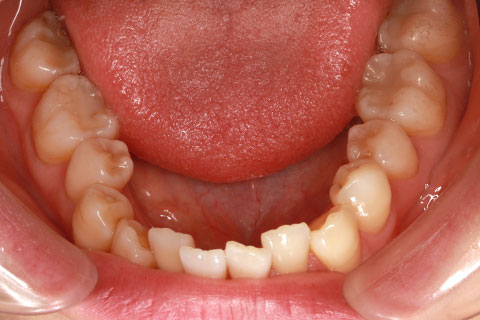

フルリンガル矯正1(上下の歯を舌側矯正で治療)

治療前

治療中

治療後

- 年齢・性別

- 33歳女性

- 治療期間

- 2年0ヶ月

- 抜歯

- 上顎4番抜歯。下顎5番欠損。

- 治療費

- 120万円(税込み)

- 備考

- フルリンガル矯正

- 治療内容

- 上顎前歯の叢生改善および下顎前歯の空隙閉鎖

- 施術の副作用(リスク)

- 装置が裏側について、目視ができないため、しっかりとブラッシングができているかどうかわかりにくい。